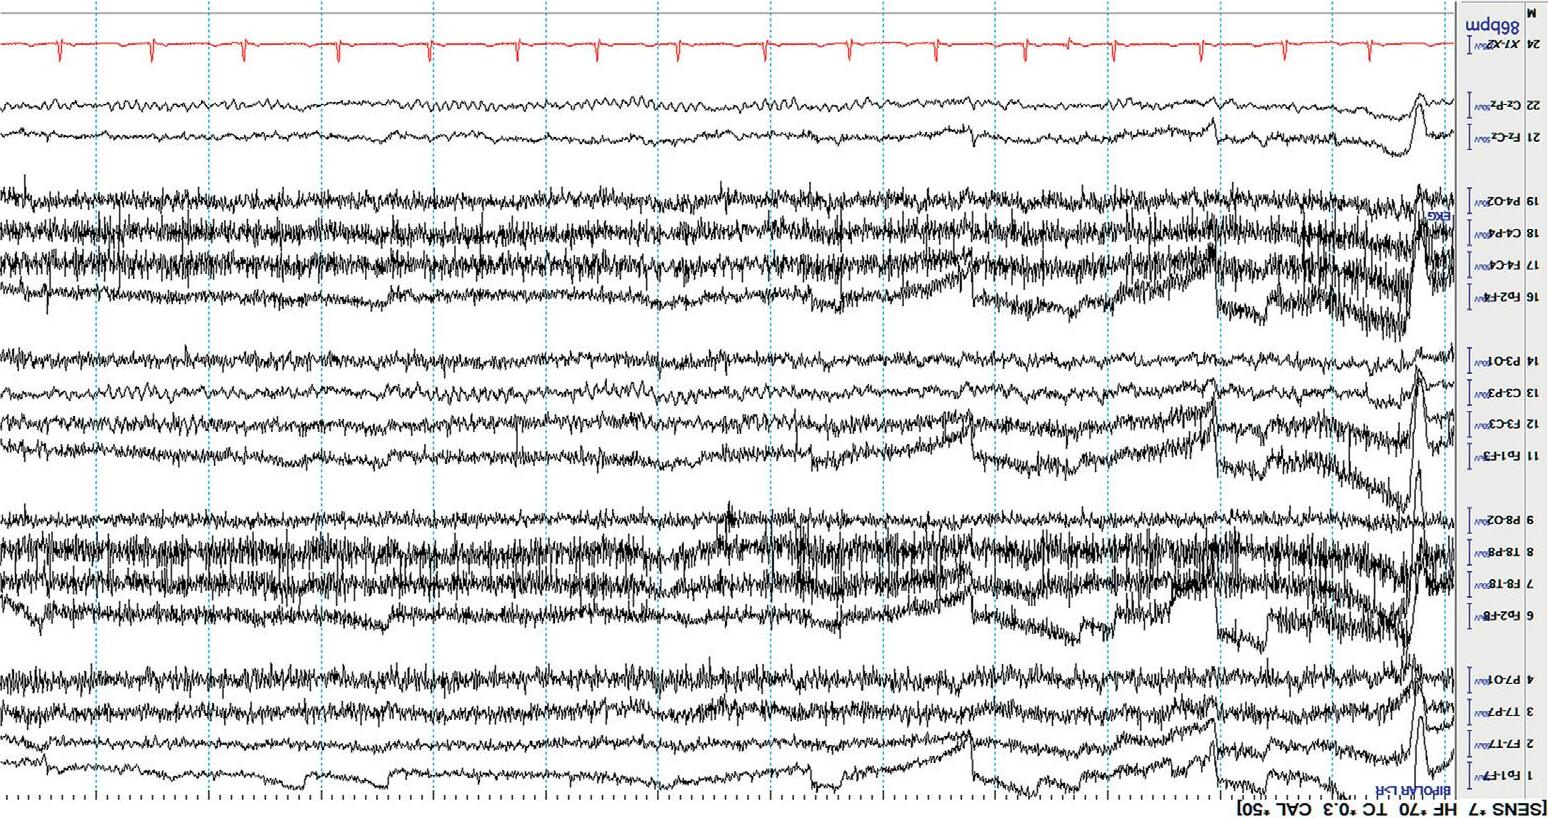

Drowsy Asthepatientbecomesdrowsy(N1sleep),the alpharhythmscanslowand becomemoreintermittent,thebackground amplitudedecreases,the frequencyslows,and slowlateral(“ roving ”)eyemovements canappear. Eyeblinksandmuscleartifactdisappear. Figure1.7 showstheEEG duringdrowsiness.

Sleep

Lightsleepshowsfurtherslowingofthebackgroundfrequencies. StageN2 sleep isidentifiedbythepresenceof sleepspindles and K-complexes.Sleep spindlesaretransient,frontocentralpredominant,spindle-shapedburstsof 12– 16Hzactivity,whileK-complexesarecomposedofahighamplitude, centrallypredominant,generalizedwave,oftenfollowedbyabriefburstof spindleactivity. Figure1.8(a) showsstageN2sleep.

StageN3or slowwavesleep ischaracterizedbyhighamplitude,generalized,semirhythmicdeltaslowing[ 4].Rapideyemovement(REM)sleepis seldomseenintheICU. Figure1.8(b) showsstageN3orslowwavesleep.

Figure1.7 NormaldrowsyEEG;blackarrowmarksanormal “vertexwave.”

Figure1.8(a) NormalstageN2sleep;thebluearrowmarksanormalsleepspindle,andtheredarrowmarksanormalK-complex.

Figure1.8(b) NormalstageN3sleep(slowwavesleep).